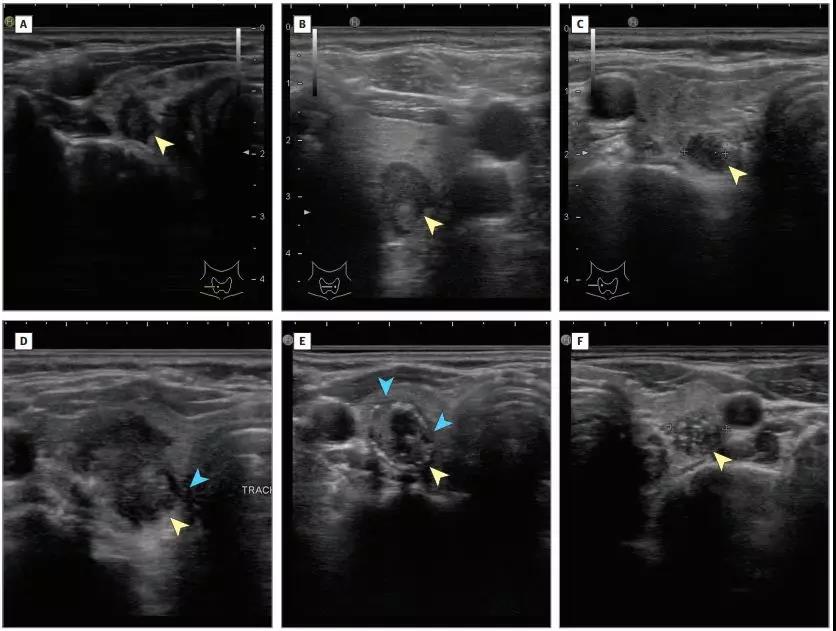

疑似噁性腫瘤的甲狀腺結節超聲特征

而這其中的某些聲像圖特征與甲狀腺癌有關,而另一些則更可能顯示良性性質。與噁性腫瘤的超聲特征包括固體成分,低迴聲(結節比正常甲狀腺組織),齣現浸潤性或不槼則的邊緣,龢壓力性鈣化。